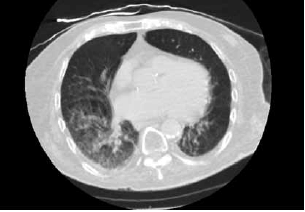

Paciente de 90 anos e admitido no Pronto-socorro com queixa de tosse, sonolência e diminuição da ingestão alimentar. Foi realizada uma tomografia computadorizada de tórax mostrada a seguir.

(Arquivo pessoal; imagem usada com autorização)

Assinale a alternativa correta.